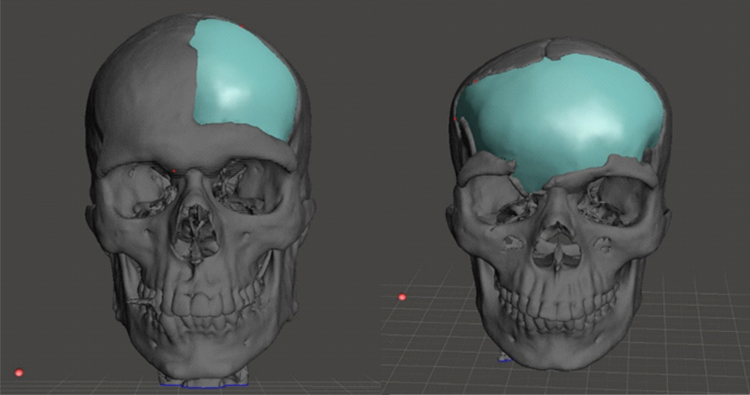

- Custom Made Cranial Implant

- Craniofacial Implants

CONSTRUCTION OF A 3D-IMPLANT MODEL

On the basis of the virtual 3D-patient model an implant model is constructed. After consultation between you, the treating physician, and our technical designers, you determine the final implant shape. The consultation can take place either via telephone or via E-mail. If necessary we send you also real 3D- model for the implant planning.

A perfect fit implant as per your patient anatomy

PATIENT SPECIFIC IMPLANTS

Patient-specific implants are designed and produced according to patient-derived CT data for excellent reconstructive results. Our main products are patient-specific implants for the brain- and face-skull areas. These patient-specific implants can, for example, become a necessity after trauma, tumour surgeries, surgery accesses. This new procedure allows us to create implants that are custom-made for every patient.

The data of the patient is prepared and converted by us; a virtual 3D-patient model is created.